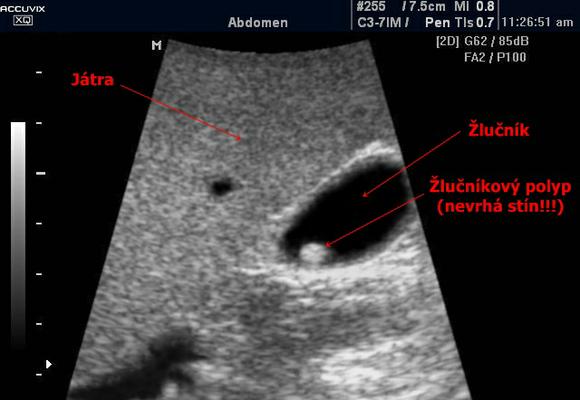

| 1 | ультразвуковое обследование (УЗИ). Такая методика существует почти в каждом лечебном учреждении и позволяет четко рассмотреть холестериновые новообразования, причем как одиночные, так и собранные в группы. Их изображение на экране предстает в виде пятен округлой формы, у которых нет акустических теней, и которые при перемене пациентом позы не смещаются |